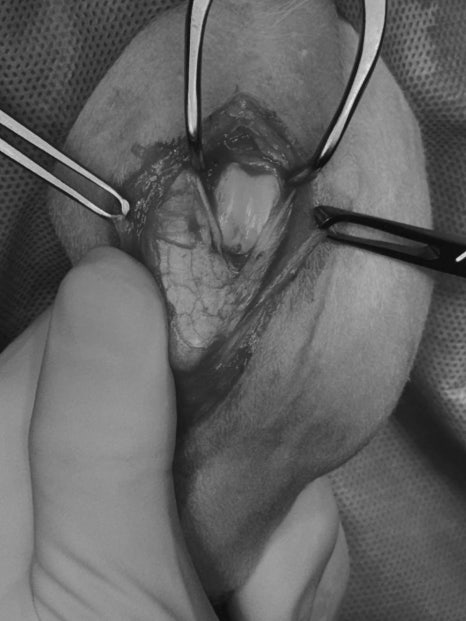

수술 및 회복 과정

슬개골수술 사진/ 출처: 라온동물메디컬센터

좌측 슬개골탈구 교정 수술은 계획에 따라 진행되었습니다. 무릎 정렬을 바로잡고 슬개골이 정상 위치에 안정적으로 유지되도록 교정했으며, 수술 과정은 특별한 합병증 없이 마무리되었습니다.